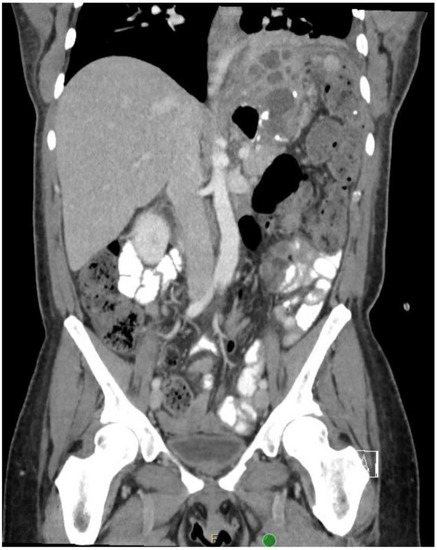

2. Detailed Case Description